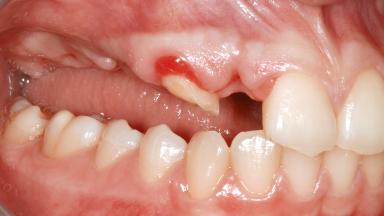

Ridge Preservation and Implant Placement for a Fixed Dental Prosthesis After a Car Accident

It is well known to clinicians that any removal of teeth will, over time, cause the dimensions of the alveolar ridge to be reduced by resorption of the bundle bone and by changes related to external modeling. This development is particularly evident in the crestal region with its thin buccal bone that consists of bundle bone almost entirely. The facial bone will rapidly resorb as blood supply from the periodontal ligament gets disrupted (Araújo and Lindhe 2005). There is no reason why traumatic tooth loss should not have the same consequences. It takes more than achieving implant osseointegration for a treatment outcome to be considered successful. No deficiency of bone or soft tissue is acceptable when an ideal esthetic outcome is the goal. Several articles (Sanz and coworkers 2011; Vignoletti and coworkers 2011) have reported on techniques of improving the alveolar ridge for implant treatment, notably focusing on protecting tissues from resorption.